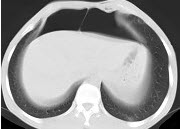

男,30岁,上腹部剧痛,恶心呕吐,压痛反跳痛,血细胞计数升高,血和尿淀粉酶升高,影像表现如图,最可能的诊断是什么( )

A:急性肠梗阻

B:胃溃疡穿孔

C:胰腺癌

D:急性胰腺炎

E:慢性胰腺炎